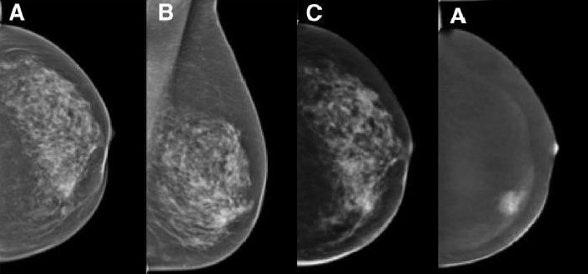

Imaging and Targeted Biopsy of Breast Cancer

Martin Daniaux

Dual-energy (DE) contrast-enhanced mammography is one of the latest developments in breast care. Imaging with contrast agents in breast cancer has been described in MRI and CT. However, high costs, limited availability and high radiation doses have led to the development of contrast-enhanced spectral mammography (CESM).

The research team focusing on the diagnosis of breast cancer has a vast wealth of experience with all the imaging modalities currently used for evaluation of the breast, including fine-needle aspiration and/or percutaneous biopsies using stereotaxis or ultrasound guidance. Our unit serves as the largest screening and assessment centre of the national breast-screening programme in Tyrol. Approximately 10,000 mammograms and breast ultrasound studies are performed each year.